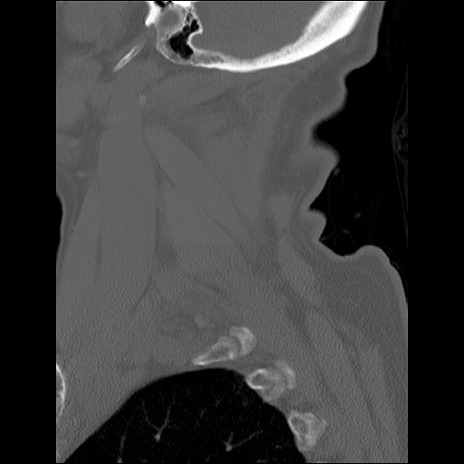

症例48 頚椎CT(矢状断像)

頚椎CT